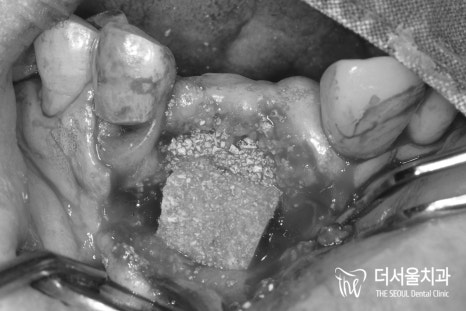

더서울에서는 말씀드렸던 내용을 토대로

치조골 소실이 꽤 심한 상태였기 때문에

이식하는 자체에도 어려움이 있었는데요.

모자란 곳에 보강을 해준 뒤,

5개월의 기간을 두어

회복을 기다리기로 했습니다.